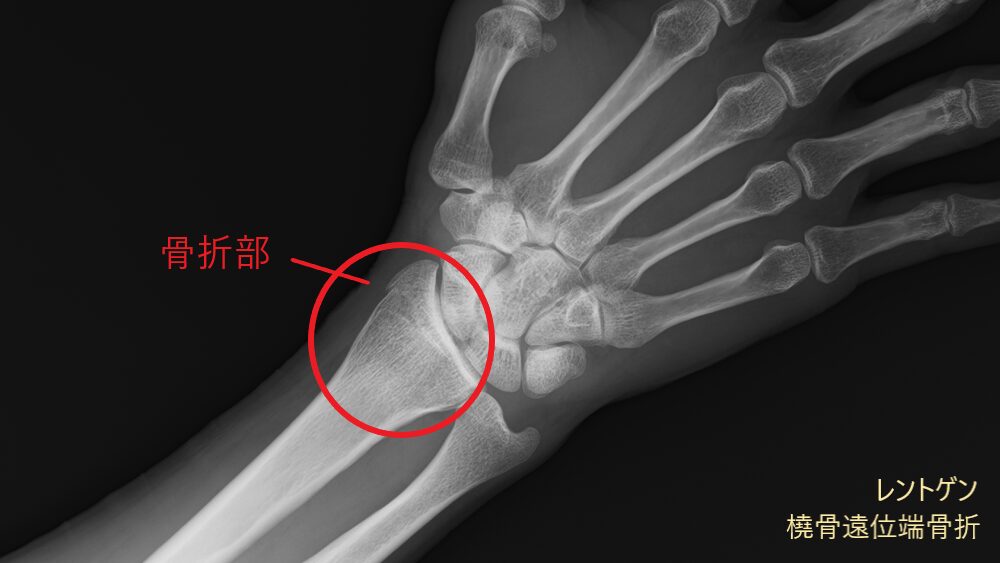

レントゲン画像には映りにくい筋肉や腱、靭帯などの状態に加え、骨の様子もあわせて確認できます。